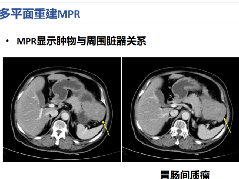

【影像表现】 钡灌肠:直肠与乙状结肠起始部可见不规则充盈缺损(图1箭头),肠管见偏心性狭窄;粘膜皱襞紊乱,纠集(图2、3箭头)。 CT:直肠壁不均匀增厚,见软组织影突入直肠腔内,增强扫描中度强化,周围脂肪间隙欠清楚,直肠后方可见肿大淋巴结(箭头)。肝脏体积增大,肝内密度欠均匀,可见多发弥漫不均匀低密度区,增强扫描病灶显示更加清楚,呈多发结节样低密度影,脾周及胆囊窝周围可见少量液性低密度影。

CT:(1)肠壁增厚,增厚的肠壁黏膜面多明显凹凸不平。(2)腔内肿块影,偏心性,呈分叶状或不规则形,与正常肠壁分界清楚,肿块表面可见小溃疡,呈火山口样。(3)肠腔狭窄,且为非对称性。(4)增强扫描可见较明显异常强化。(5)浆膜及临近器官受侵表现。

MRI:T1WI低或等软组织信号影,T2WI肿瘤信号增高,接近或高于脂肪组织的信号强度,增强扫描可见轻~中度强化。其他表现同CT。